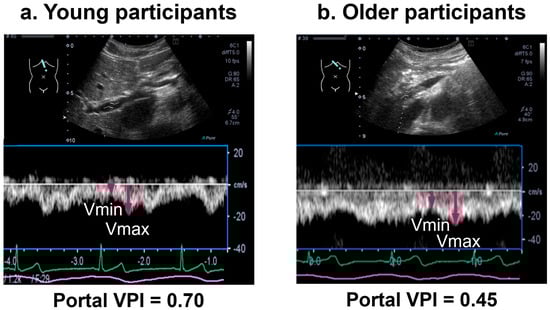

| Portal maximum flow velocity * (cm/s) | 46 ± 25 | 41 ± 28 | 0.430 |

| Portal minimum flow velocity * (cm/s) | 15 ± 11 | 24 ± 14 | 0.007 |

| Portal VPI | 0.65 ± 0.15 | 0.34 ± 0.16 | <0.001 |

| Portal VPI ≥ 0.3, n (%) | 29 (97) | 15 (58) | 0.029 |

| Portal VPI ≥ 0.5, n (%) | 27 (90) | 4 (15) | <0.001 |